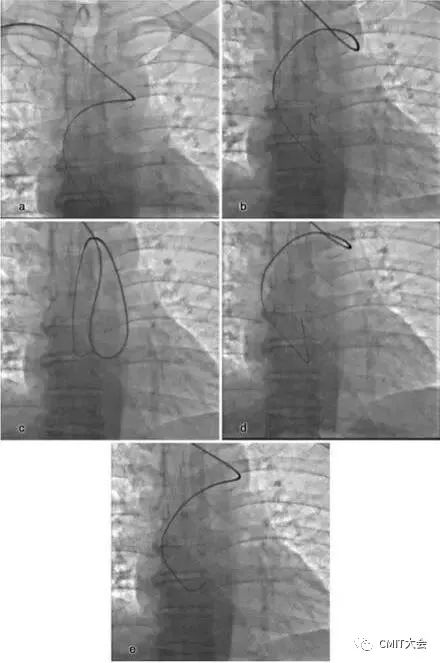

1. 桡动脉迂曲

桡动脉迂曲在TRI中是一常见问题,约占3.8%~4.2%,桡动脉迂曲的部位在桡动脉近心端三分之一处,老年及女性患者的发生率要明显高于其他人群。根据桡动脉迂曲的形态可进一步将其细分“S”、“α”、“Ω”以及“Z”等多种类型,其中以“S”和“Ω”形迂曲最为常见,不同类型的桡动脉迂曲处理难度亦不相同,例如桡动脉“S”形迂曲的处理相对较为容易,其操作成功率要高于其它类型的桡动脉迂曲。

“S”

“α”

“Ω”